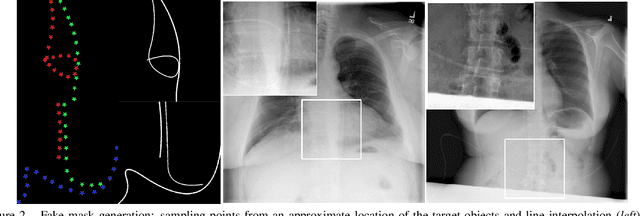

Abstract:Chest X-ray is one of the most widespread examinations of the human body. In interventional radiology, its use is frequently associated with the need to visualize various tube-like objects, such as puncture needles, guiding sheaths, wires, and catheters. Detection and precise localization of these tube-like objects in the X-ray images is, therefore, of utmost value, catalyzing the development of accurate target-specific segmentation algorithms. Similar to the other medical imaging tasks, the manual pixel-wise annotation of the tubes is a resource-consuming process. In this work, we aim to alleviate the lack of the annotated images by using artificial data. Specifically, we present an approach for synthetic data generation of the tube-shaped objects, with a generative adversarial network being regularized with a prior-shape constraint. Our method eliminates the need for paired image--mask data and requires only a weakly-labeled dataset (10--20 images) to reach the accuracy of the fully-supervised models. We report the applicability of the approach for the task of segmenting tubes and catheters in the X-ray images, whereas the results should also hold for the other imaging modalities.